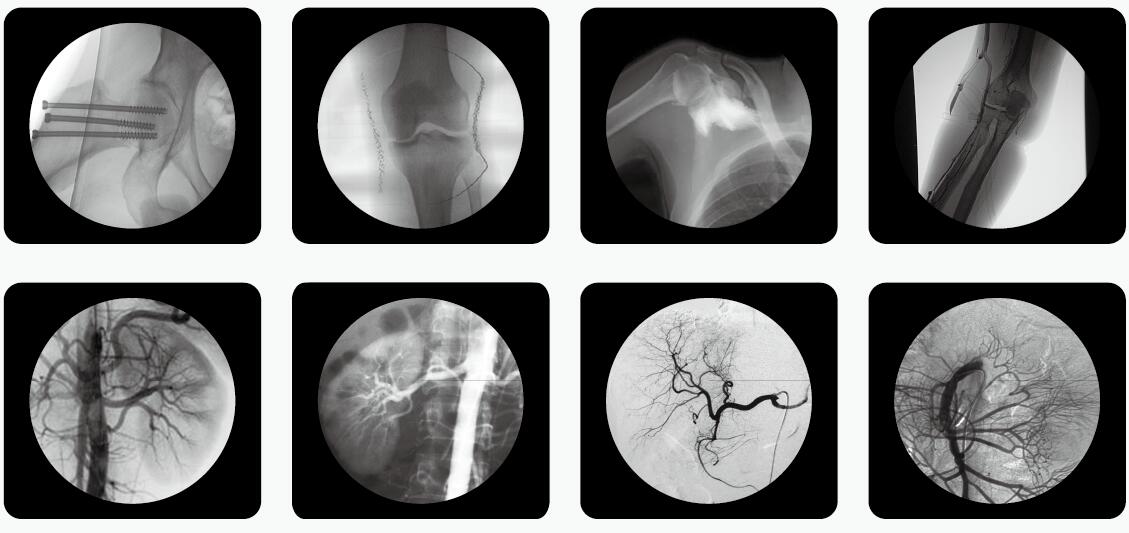

如何在滿足影像診療質量的同時,有效地控制輻射危害,已成為放射學發(fā)展中的一個亟待解決的重要問題。C臂透視機是骨科手術中使用較多的一款放射性醫(yī)療設備。

C臂透視機

骨科醫(yī)生用C臂機透視比較多,如何在手術過程中實施安全防護措施,極大限度地減少電離輻射對人體的危害,顯得尤為重要,以下是小編為大家整理了C臂透視機防護三大原則,來和大家一起分享。